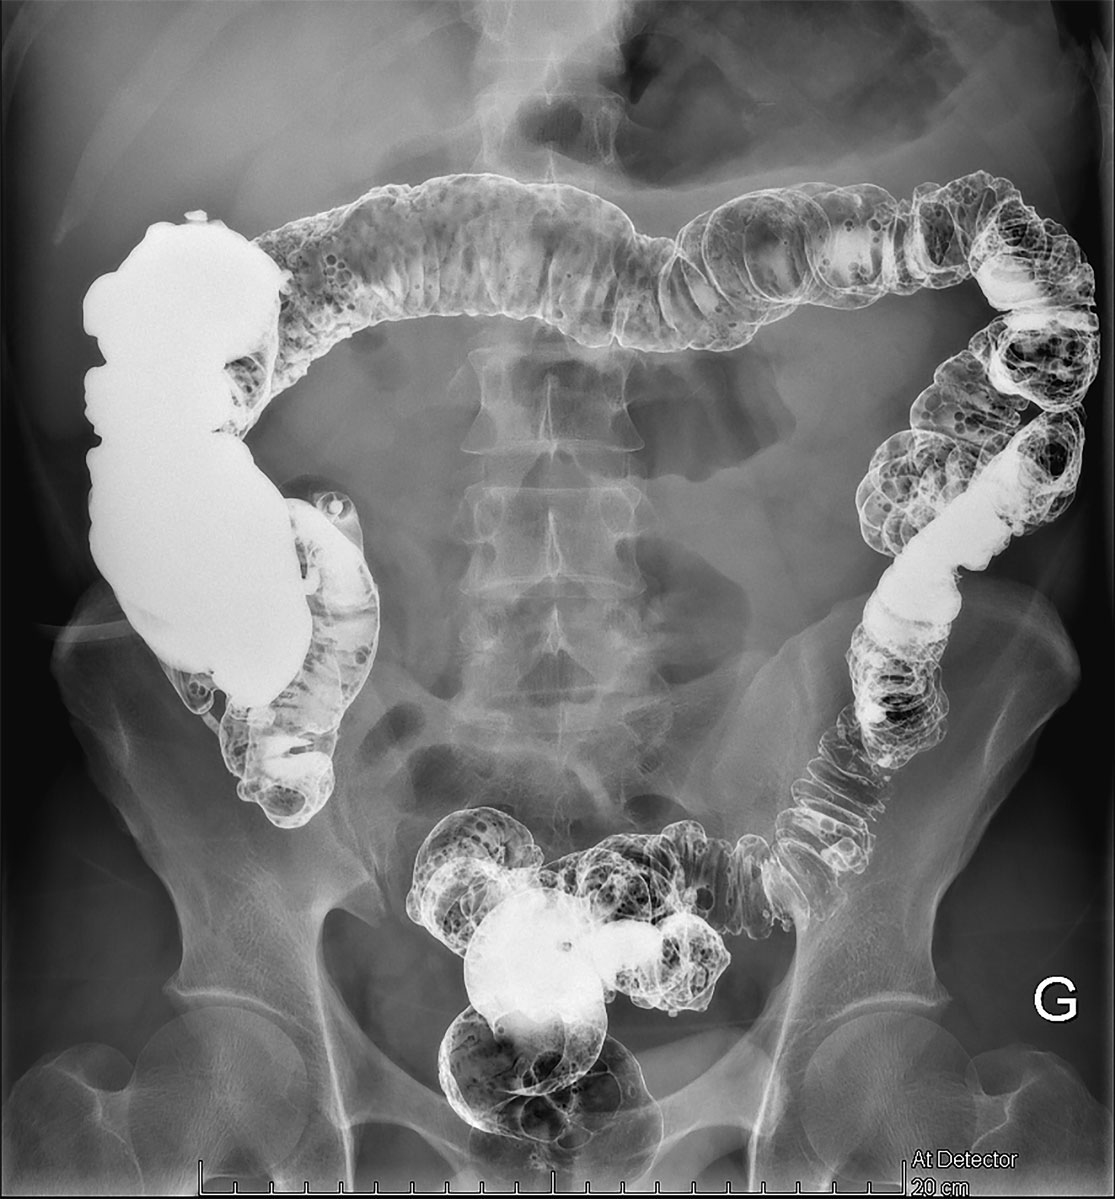

A follow-up consultation 1 month later confirmed an excellent clinical evolution, with no evidence of abdominal pain, bowel disorders or poor wound healing. Eight weeks later, a barium enema was performed, and no signs of stenosis were found (fig. 6). Six months following the creation of the ostomy, restoration continuity was performed using the former ileostomy site. The postoperative period was simple and the patient was discharged home nine days later.

Figure 6 Abdominal radiography with barium enema through the ostomy showing no signs of stenosis